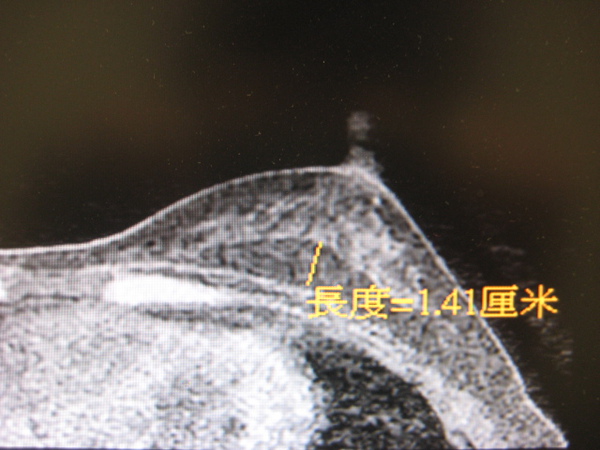

水刀抽脂自體脂肪移植手術半年後經由核磁共振檢查

自體脂肪存活無異狀無鈣化

自體脂肪存活區域與乳腺無影響